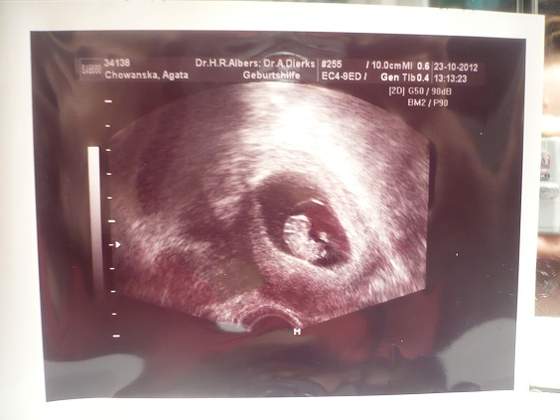

Opisze tak szybko ostatnią wizytę, we wtorek. Był ze mną mąż

wiadomo że się bardzo denerwowała, ale lekarz sobie żartował i jak zobaczyłam skaczącego maluszka to mi minęło

Maleństwo ma 5,6 cm od głowy do pupy, rączki, nóżki i jest cudne

przeziernosć 15 mm :-) no tak się ruszał, i skakał, i pływał, prostował nóżki i podkurczał- normalnie czad!

W dodatku lekarz wyliczył że maluch ma 12 t i 6 dni (a według OM miałby mieć 12 t i 4 dni) a na ostatniej wizycie 4 tygodnie temu był o tydzień młodszy w stosunku do daty OM. Czyli nadrobił

Wcześniej był termin na 11 maja, a teraz na 1! Następna wizyta za 4 tygodnie. A mam do Was pytanie - czy któraś z Was chodzi do dwóch lekarzy, bo ten teraz był prywatnie a ja chodze jeszcze na nfz?